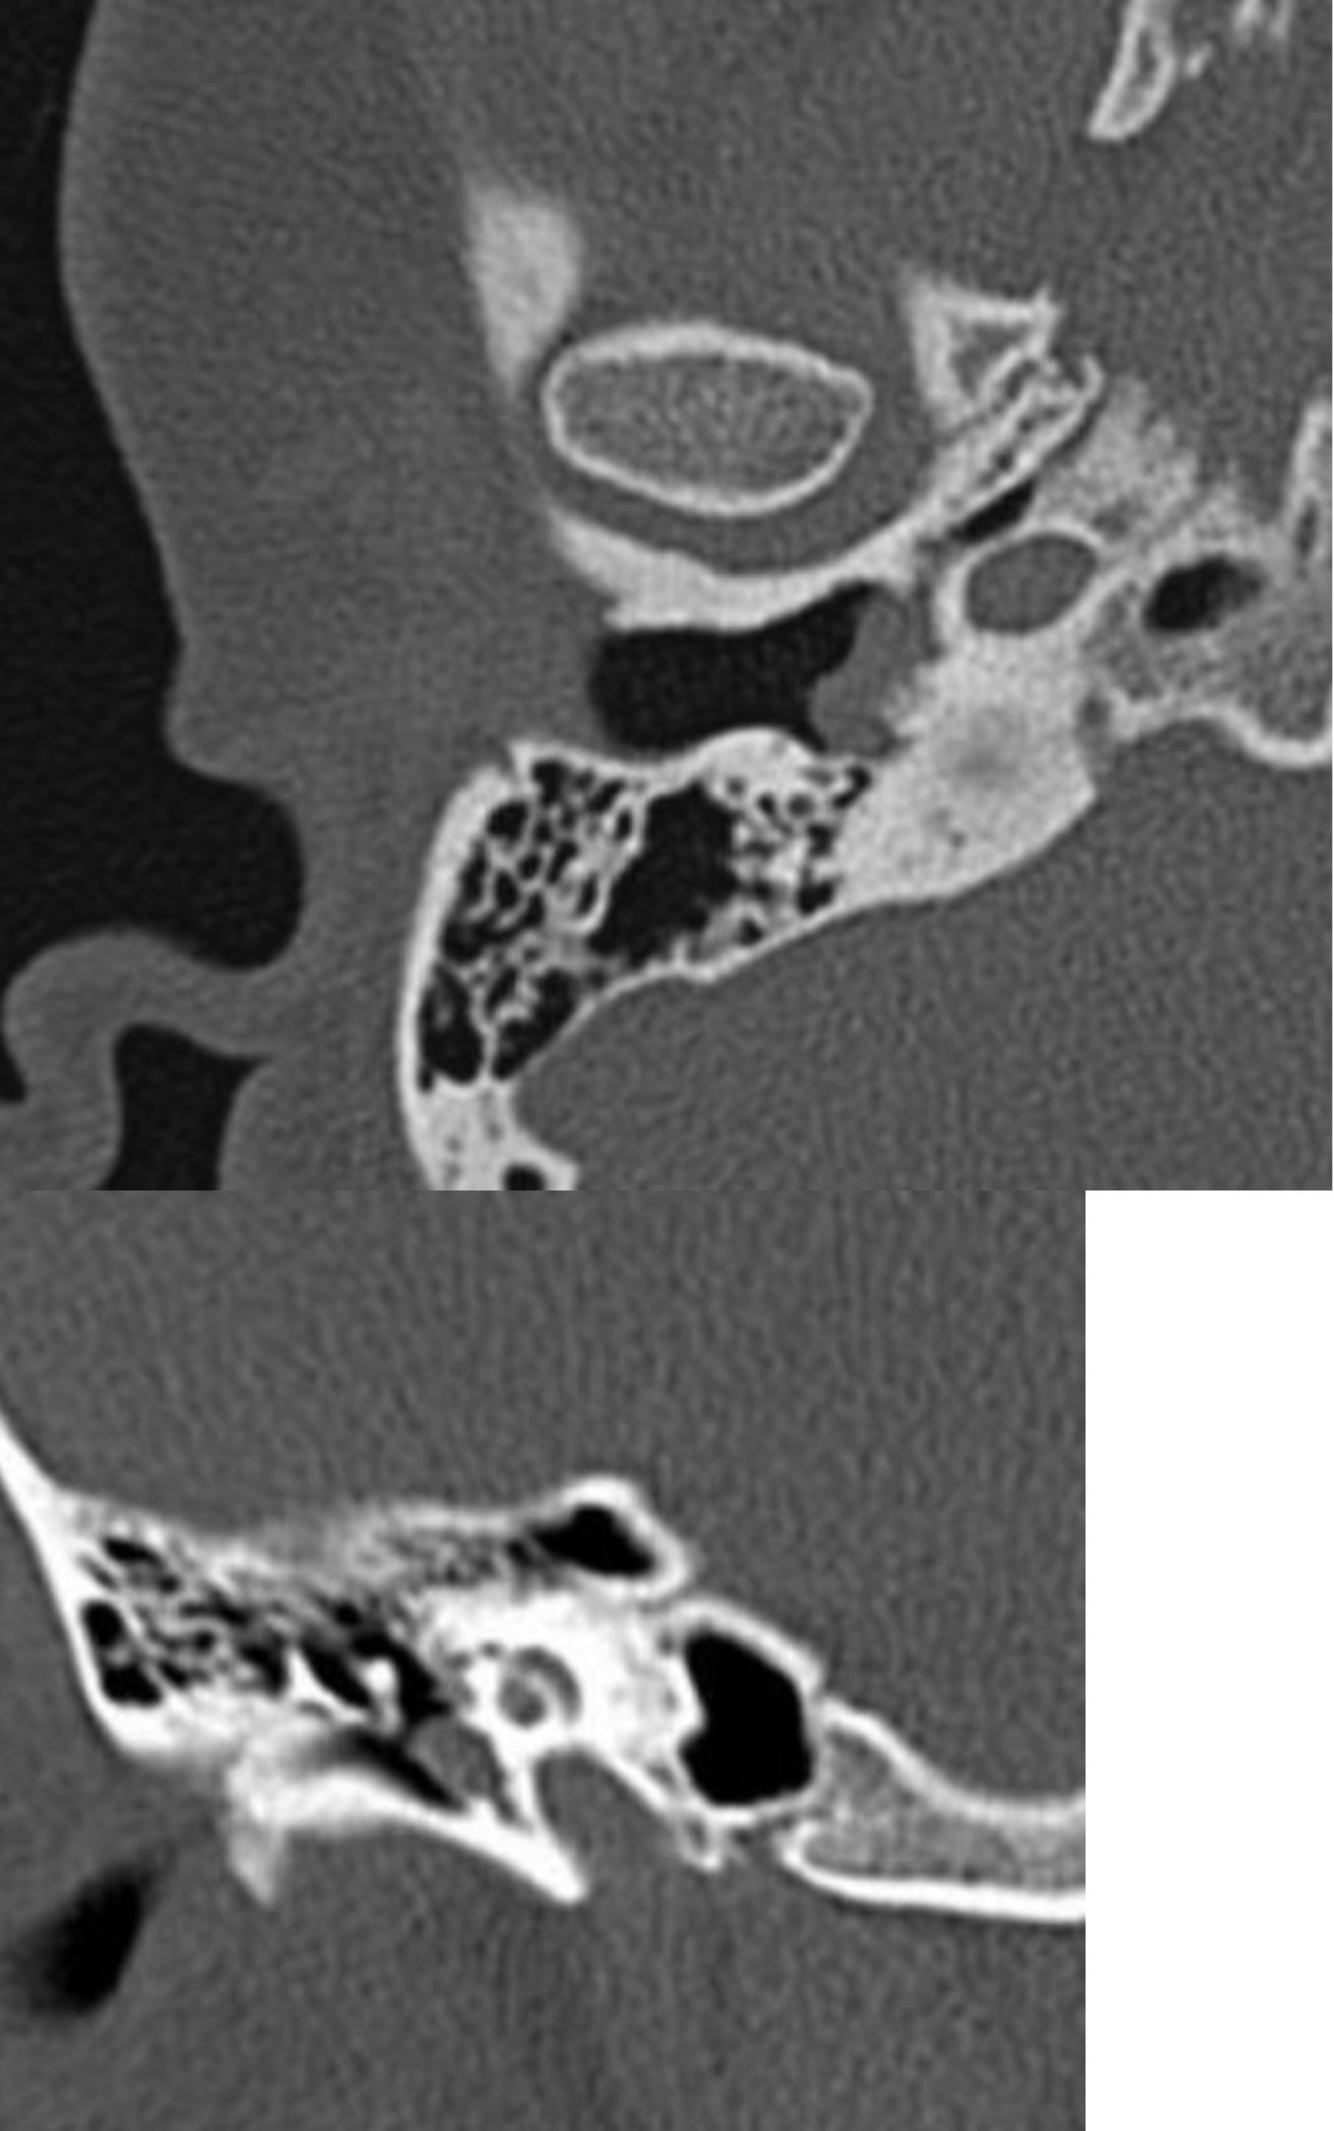

In a patient with atresia of the EAC, the FN tends to be dehiscent in the ___ segment and can overlie the ___.

In a patient with atresia of the EAC, the FN tends to be dehiscent in the tympanic segment and can overlie the oval window.